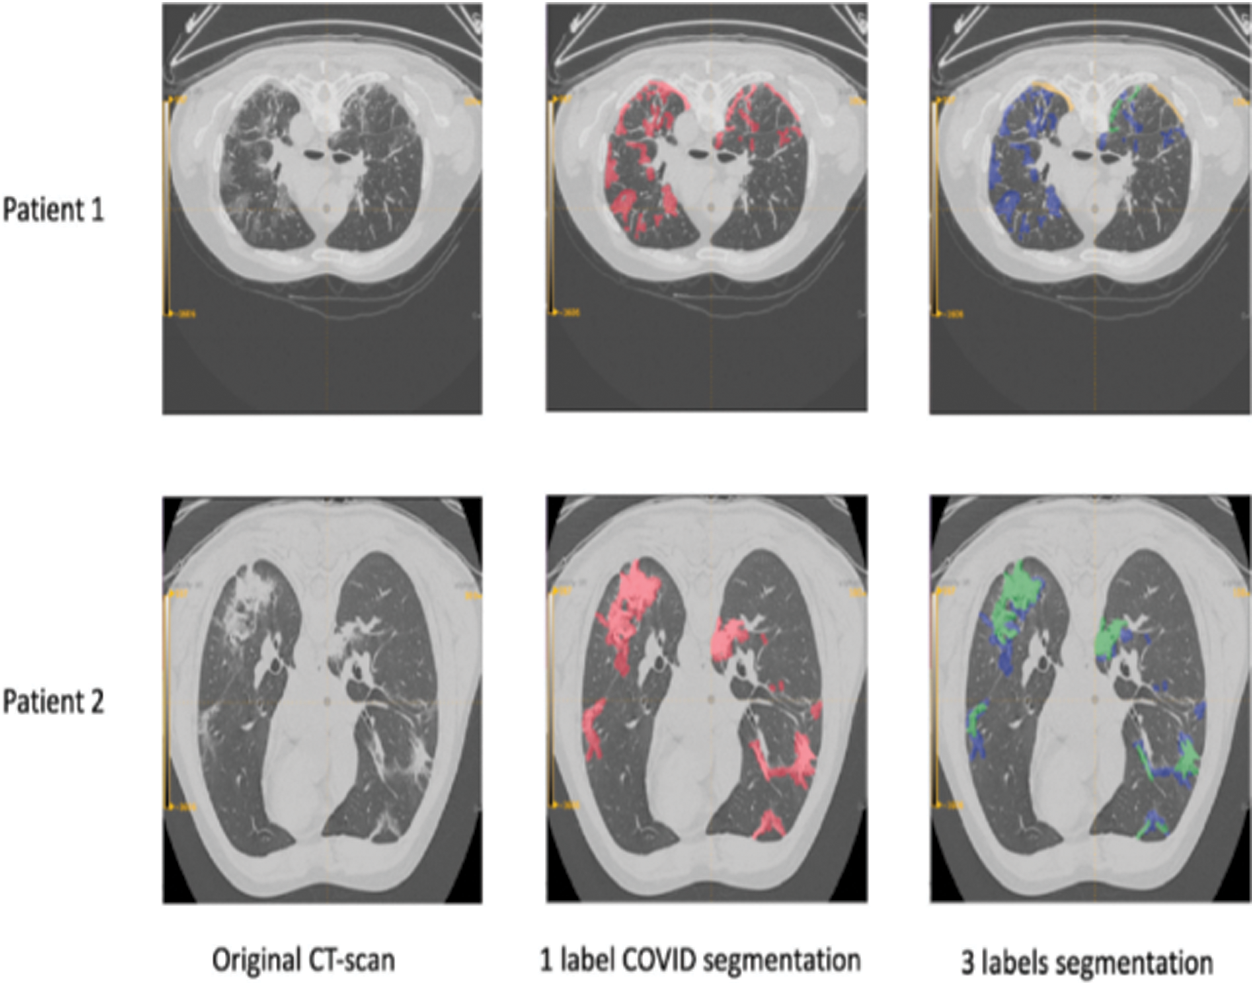

The main concept is that in the classification of images, the vertical or horizontal edge findings are achieved by executing a convolution function. A small window is considered a filter and starts to enhance the image. The filter induces Inception v4 CNN to detect the specified patterns in the image. Fig. 3 shows segmented outcome of covid 19 CT images.

Figure 3: Segmented outcome of covid 19 CT image